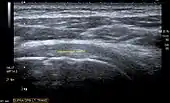

Ultrasound

There are several advantages of ultrasound. It is relatively cheap, does not emit any radiation, is accessible, is capable of visualizing tissue function in real time, and allows the performance of provocative maneuvers in order to replicate the patient’s pain.[26] Those benefits have helped ultrasound become a common initial choice for assessing tendons and soft tissues. Limitations include, for example, the high degree of operator dependence and the inability to define pathologies in bones. One also has to have an extensive anatomical knowledge of the examined region and keep an open mind to normal variations and artifacts created during the scan.[27]

Although musculoskeletal ultrasound training, like medical training in general, is a lifelong process, Kissin et al. suggests that rheumatologists who taught themselves how to manipulate ultrasound can use it just as well as international musculo-skeletal ultrasound experts to diagnose common rheumatic conditions.[28]

After the introduction of high-frequency transducers in the mid-1980s, ultrasound has become a conventional tool for taking accurate and precise images of the shoulder to support diagnosis.[29][30][31][32][33]

Adequate for the examination are high-resolution, high-frequency transducers with a transmission frequency of 5, 7.5, and 10 MHz. To improve the focus on structures close to the skin an additional "water start-up length" is advisable. During the examination the patient is asked to be seated, the affected arm is then adducted and the elbow is bent to 90 degrees. Slow and cautious passive lateral and/or medial rotations have the effect of being able to visualize different sections of the shoulder. In order to also demonstrate those parts which are hidden under the acromion in the neutral position, a maximum medial rotation with hyperextension behind the back is required.[34]

To avoid the different tendon echogenicities caused by different instrument settings, Middleton compared the tendon’s echogenicity with that of the deltoid muscle, which is still lege artis.[35][36]

Usually the echogenicity compared to the deltoid muscle is homogeneous intensified without dorsal echo extinction. Variability with reduced or intensified[37] echo has also been found in healthy tendons. Bilateral comparison is very helpful when distinguishing and setting boundaries between physiological variants and a possible pathological finding. Degenerative changes at the rotator cuff often are found on both sides of the body.[38] Consequently, unilateral differences rather point to a pathological source and bilateral changes rather to a physiological variation.[36]

In addition, a dynamic examination can help to differentiate between an ultrasound artifact and a real pathology.[39]

To accurately evaluate the echogenicity of an ultrasound, one has to take into account the physical laws of reflection, absorption and dispersion. It is at all times important to acknowledge that the structures in the joint of the shoulder are not aligned in the transversal, coronal or sagittal plane, and that therefore during imaging of the shoulder the transducer head has to be held perpendicularly or parallel to the structures of interest. Otherwise the appearing echogenicity may not be evaluated.[40]

![]() Transversal ultra sonography of the supraspinatus tendon |